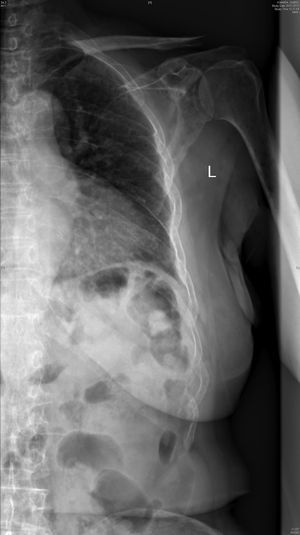

Radiología. La radiografía de cráneo muestra lesiones líticas (fig. 1). La radiografía anteroposterior y lateral de columna dorsolumbar: acuñamiento vertebrales en D7 y D11 con cambios degenerativos. Radiografía de parrilla costal anteroposterior izquierda: presencia de un patrón permeativo difuso en costillas, escápula y húmero (fig. 2).